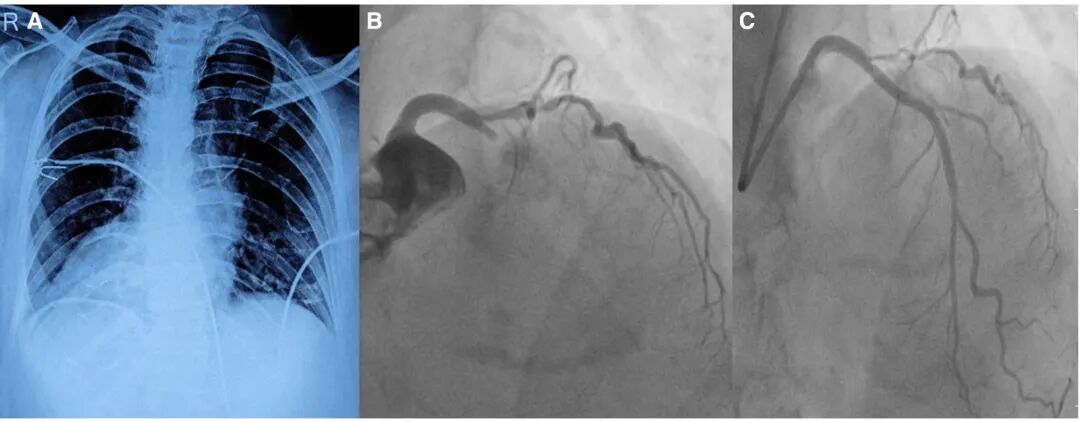

胸部X线片(图3A)及床旁超声心动图

确诊右位心,可见心尖位于右侧,支气管解剖结构与腹腔脏器呈镜像改变,符合全内脏反位表现。患者接受负荷剂量抗血小板药物及他汀类药物治疗后,紧急转运行冠状动脉造影

。造影时在透视下启用反相功能校正右位心后,证实为左前降支近段闭塞(图3B)。于左前降支植入支架,实现充分血流灌注,胸痛症状缓解(图3C)。

图3 胸部X线及造影影像

A:胸部X线片示内脏反位合并右位心,心尖位于右侧胸腔,胃泡气体影亦位于右侧。B:透视下开启左右反相模式后,前后位头倾投影视图示左前降支近段闭塞。C:经皮冠状动脉介入治疗(PCI)后,左前降支血流恢复良好。